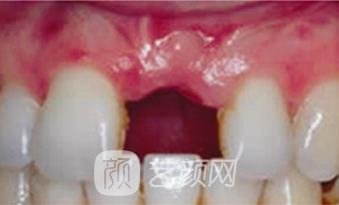

原本的牙齿就不是很齐,因为一次篮球比赛还缺失了一颗犬牙,简直是雪上加霜的事情,好在家里面的人得知了我的情况,给予了资金上的支持,让我安装一颗质量好一些的牙齿,所以挑选了德国的种植牙,虽说有一点小贵,但种植后的效果还是很满意的。